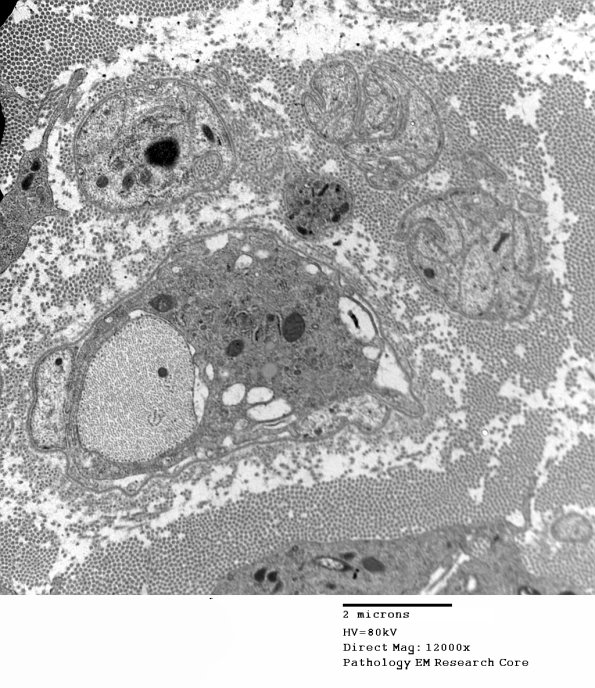

Completely demyelinated axons and scattered associated macrophages. (electron micrographs)